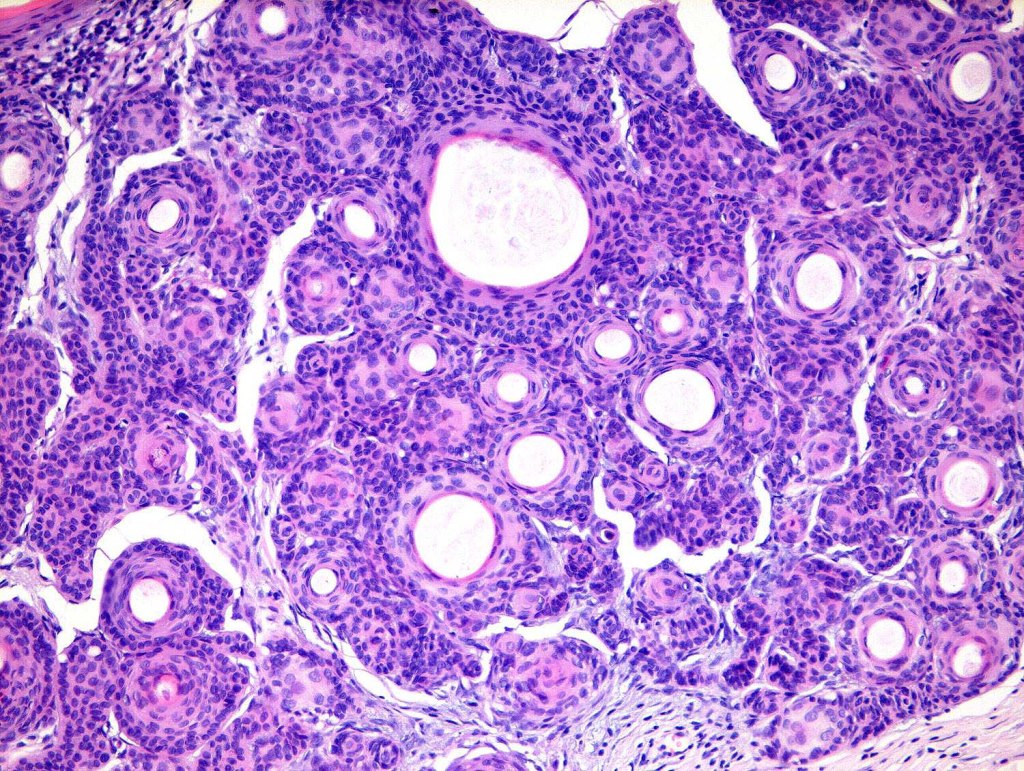

•Keratocysts showing infundibular keratinization i.e.with a granular cell layer

•Solid epithelial islands

•Fibrovascular stroma